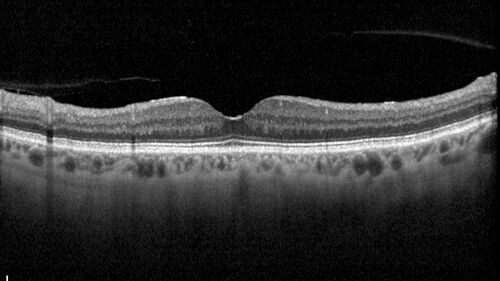

78 year old female with vision loss for 1 week and old macular scar. Images show BRAO with plaques and FA shows occlusion.

BRAO_126199_071725_07.jpg

BRAO and macular scar - plaques in vessel and video